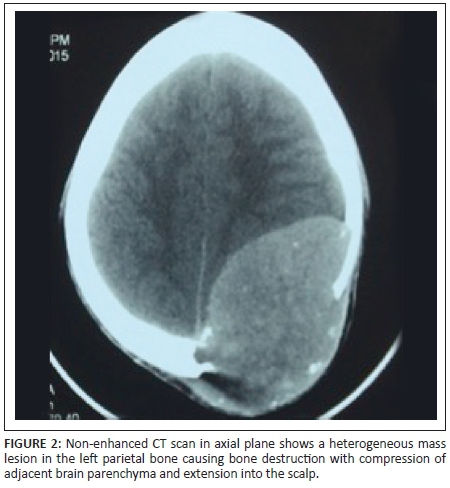

X-rays of the skull showed a well-defined lytic lesion in the left parietal bone with an associated large soft tissue component. No marginal sclerosis or periosteal reaction was noted (Figure 1a and 1b). Non-contrast computed tomography (NCCT) revealed a well-defined heterogeneous hyperdense mass lesion centred on the left parietal bone causing bone destruction, compressing the adjacent brain parenchyma and bulging into the scalp. A few small bony fragments were seen at the periphery of the lesion (Figure 2). Magnetic resonance imaging (MRI) of the brain with contrast demonstrated a well-defined heterogeneously enhancing soft tissue mass lesion measuring 8.0 cm × 7.9 cm × 6.8 cm causing destruction of the left parietal bone and bulging into the scalp. Some flow voids were seen with the mass. No restricted diffusion or surrounding oedema was noted. There was mass effect with compression of adjacent brain parenchyma and mild midline shift to the right side. The mass was compressing adjacent superior sagittal sinus but not invading it (Figures 3, 4, 5 and 6). Skeletal survey of the body revealed no other lytic lesions anywhere in the body.

On radiography, SPB presents as a well-defined osteolytic lesion with clear margins and narrow zone of transition. There is no bony sclerosis or periosteal reaction. The lesion is hyperdense on NCCT and shows marked homogenous enhancement with contrast. Small bony fragments may be seen at the periphery. On MRI, SPB appears isointense on T1-weighted images and hyperintense on T2-weighted images. Intratumoural flow voids have been described. The lesion shows dense but heterogeneous enhancement with contrast.3,5,6